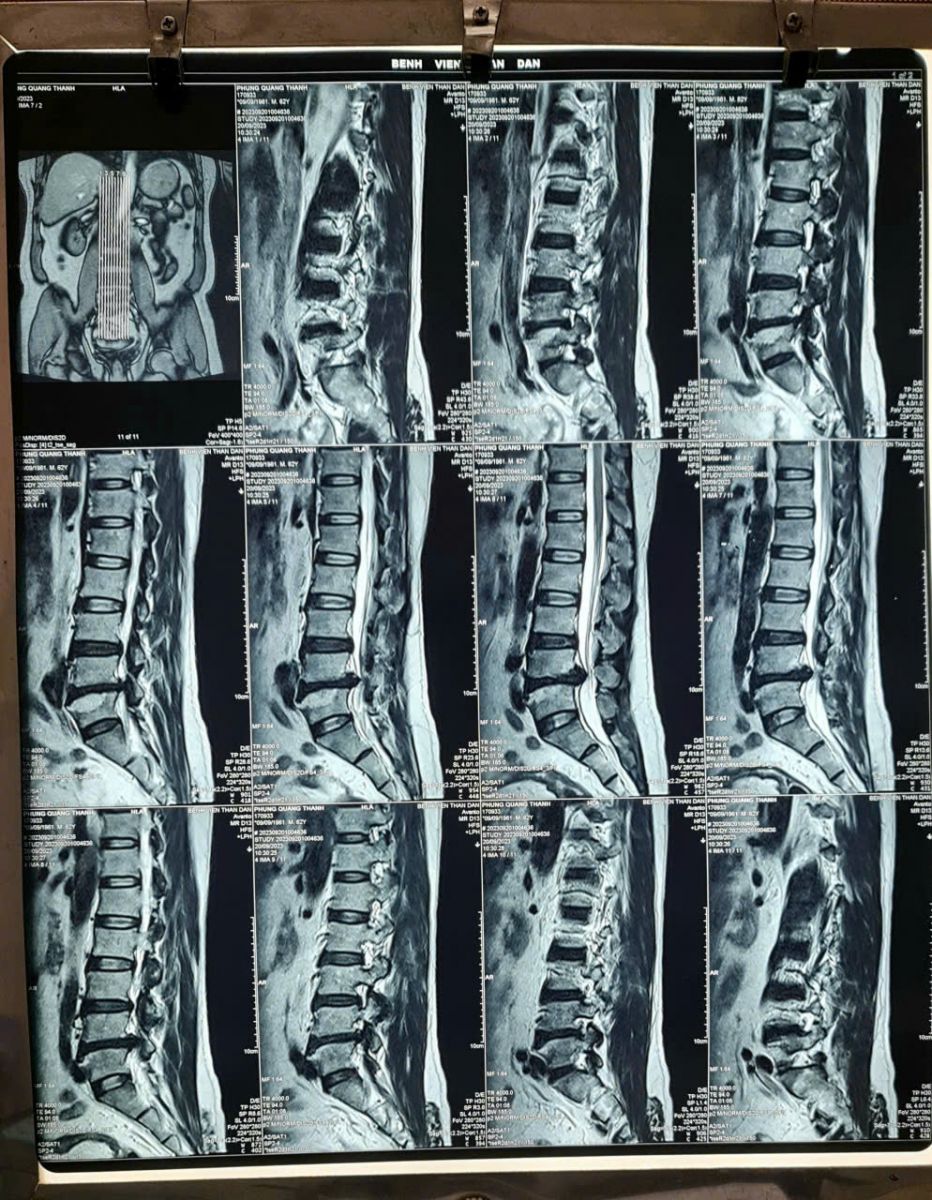

Bác Phùng Quang Thanh đồng ý chia sẻ phiếu kết quả MRI, chụp tại bệnh viện Thân Dân, TP.HCM.

Bác sĩ chụp cộng hưởng từ MRI kết luận:

- Thoái hóa cột sống thắt lưng

- Lồi đĩa đệm tầng L3-4, không chèn ép rễ thần kinh hai bên.

- Thoát vị đĩa đệm tầng L4-5, chèn ép rễ thần kinh L5, S1 hai bên

- Hẹp ống sống ngang mức L4-5, với đường kính trước sau bao màng cứng ngang mức này #4mm.

Với kết quả chụp cộng hưởng từ như trên, các bác sĩ đều khuyên bác Thanh nên phẫu thuật thoát vị đĩa đệm, nhằm giải tỏa chèn ép dây thần kinh.

Hình ảnh thoát vị đĩa đệm chèn ép dây thần kinh, của bác Phùng Quang Thanh ở Nha Trang. Cắt ra từ phim chụp cộng hưởng từ MRI cột sống.